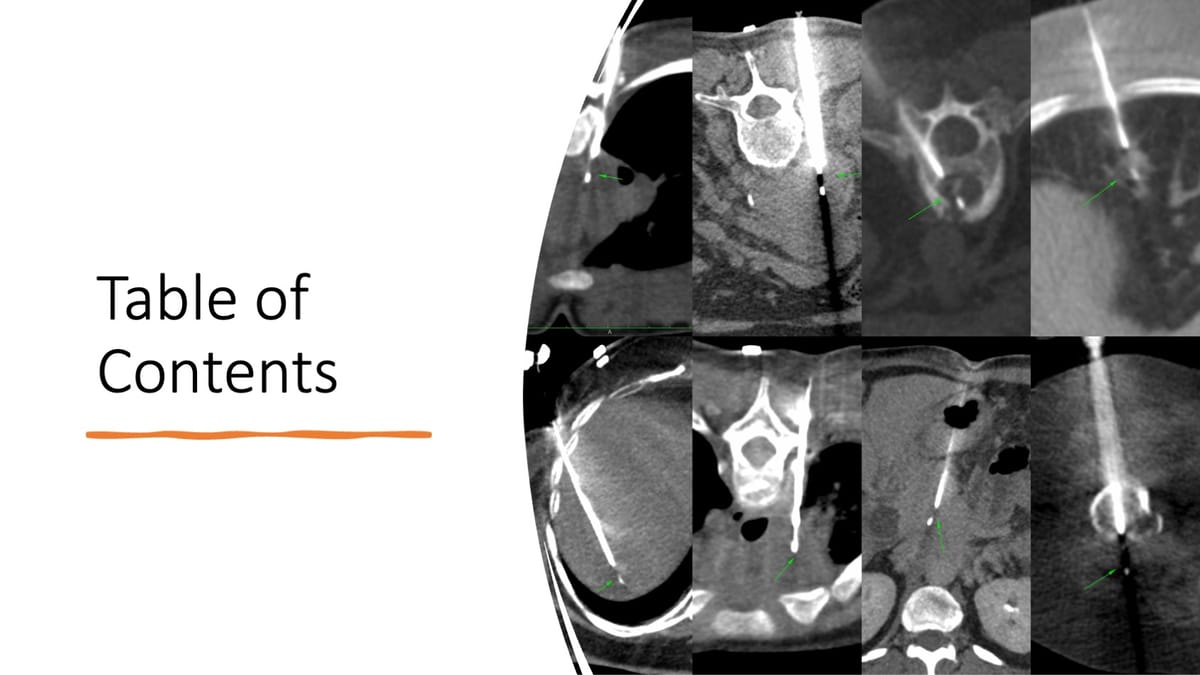

Table of Contents

All the spine biopsy posts that you can access from here